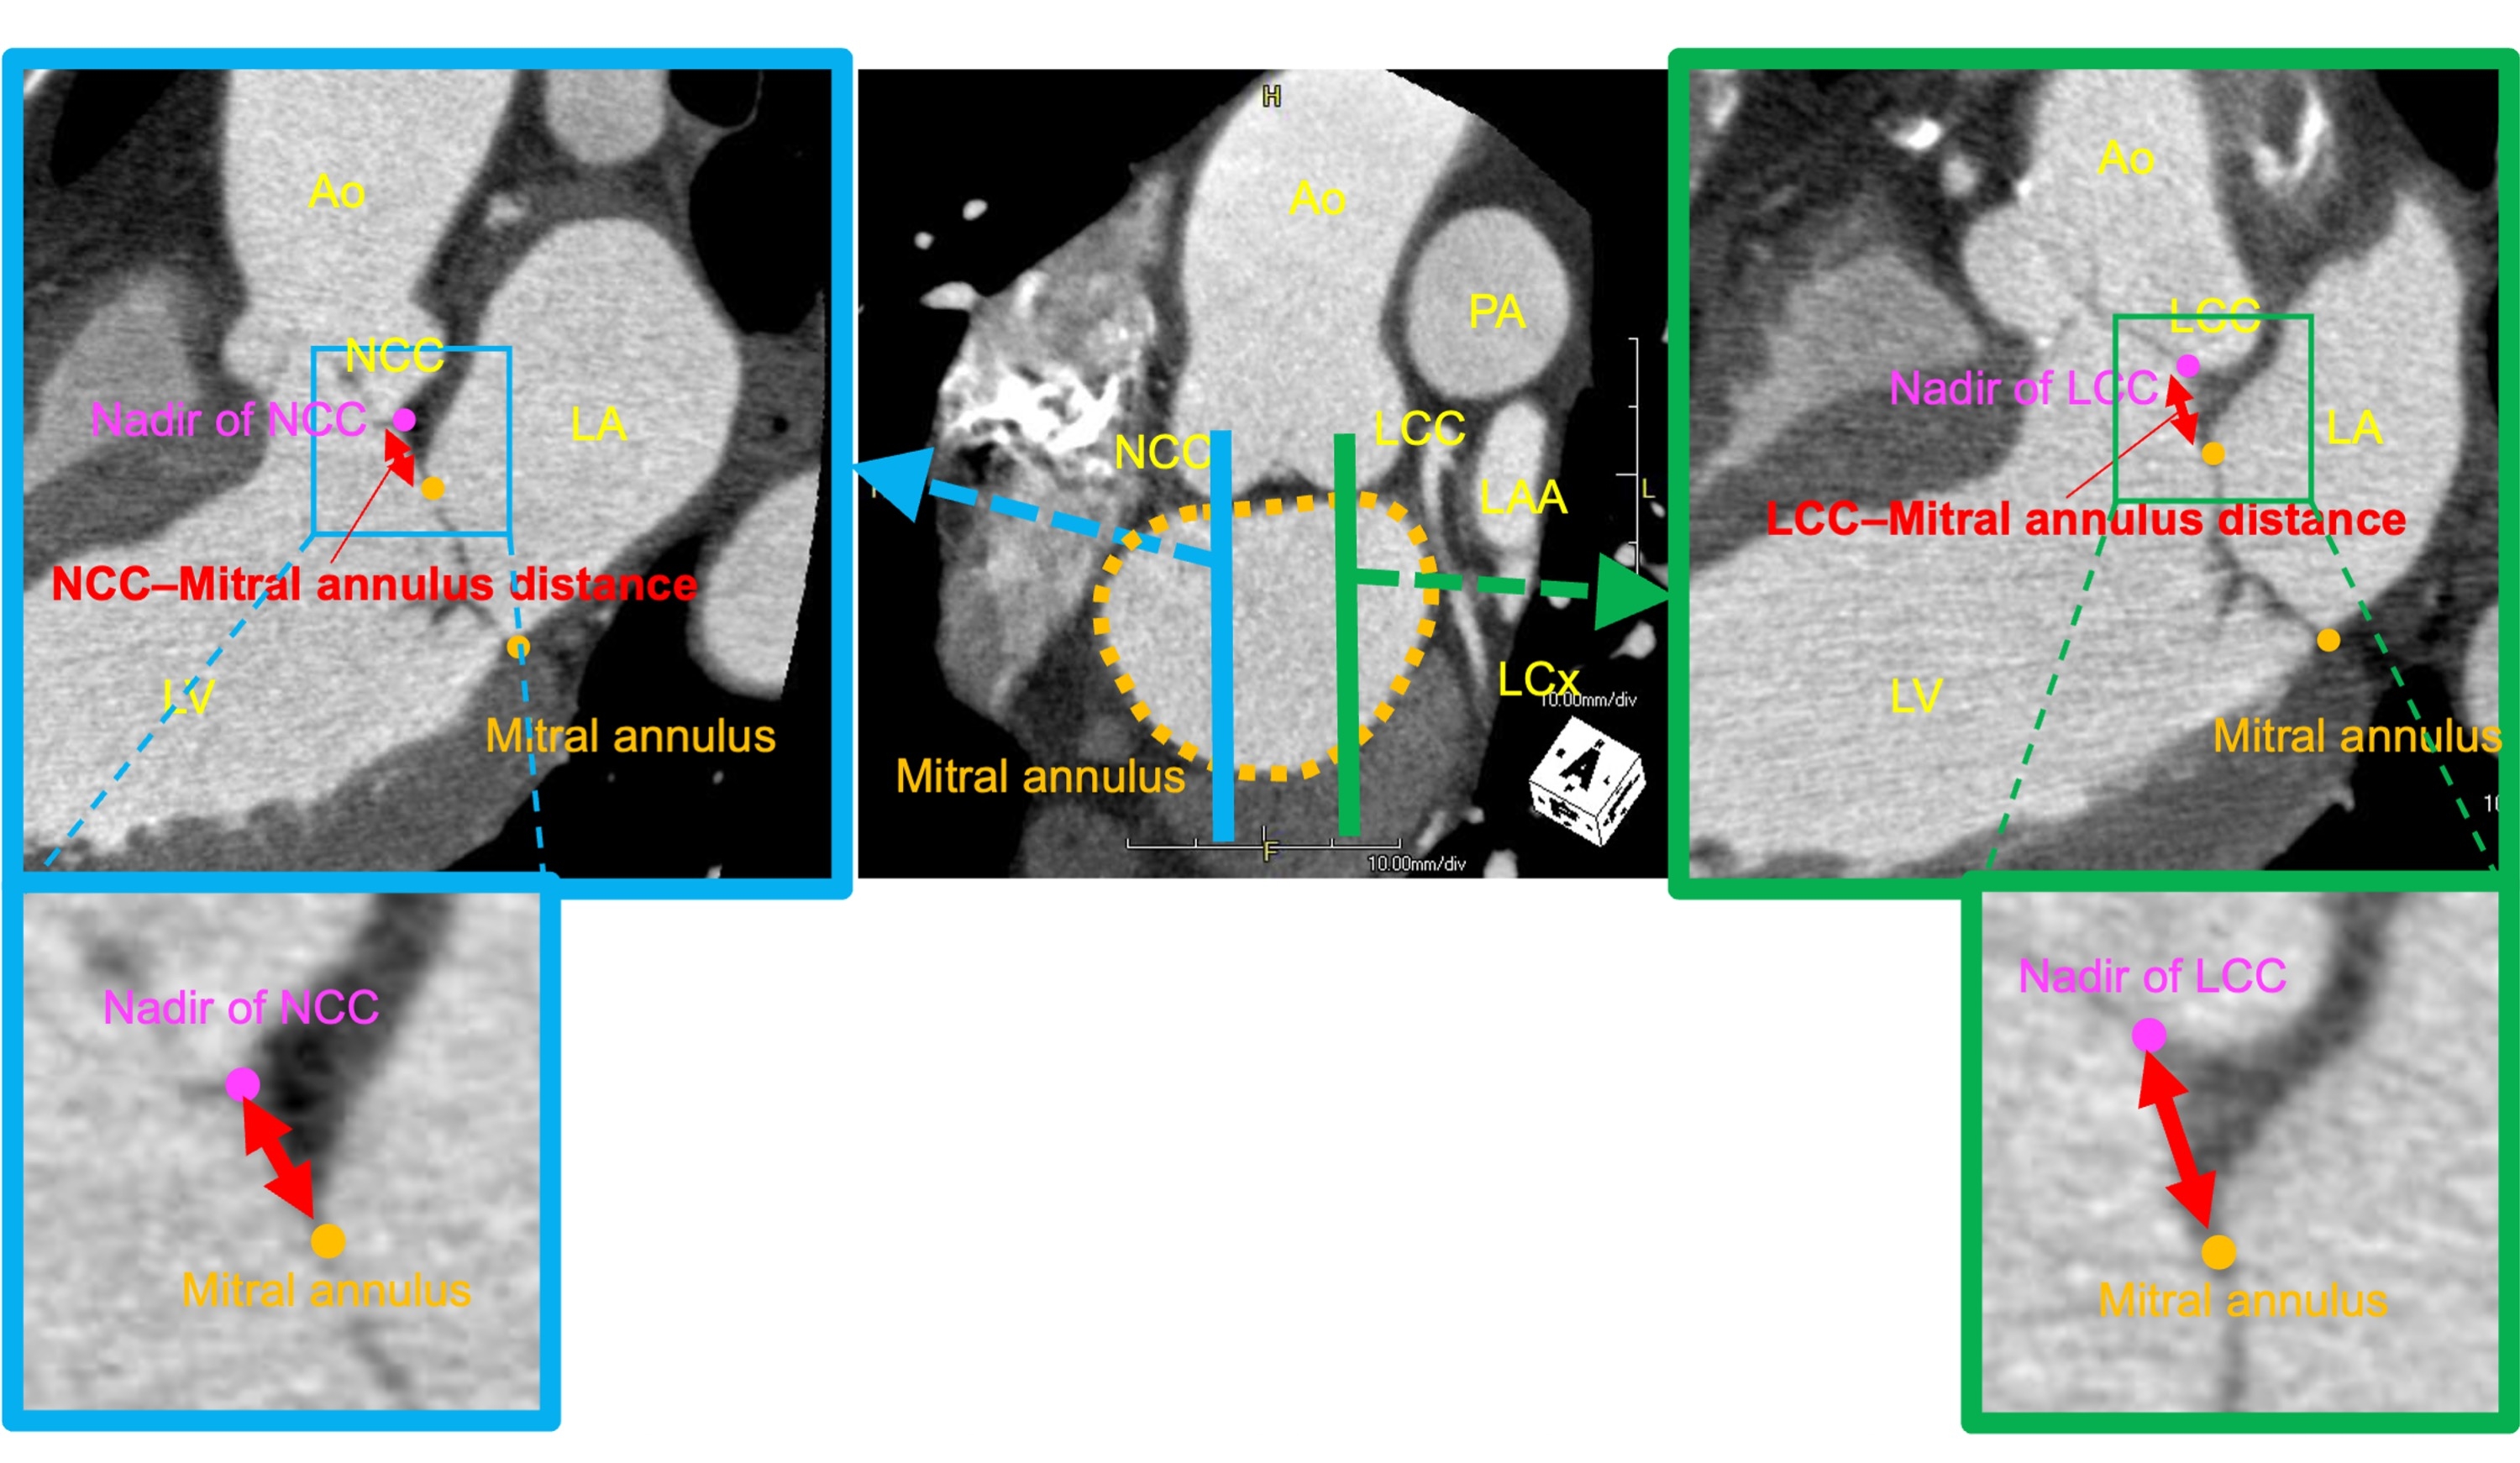

Among 857 patients who underwent mitral valve surgery between 2010–2022, those with planned concomitant aortic valve surgery, infective endocarditis, and history of aortic valve surgery (n=343) were excluded. Of the remaining 514 patients, 276 patients (53.7%) with preoperative enhanced cardiac computed tomography (CT) were included in the final analysis. The aorto-mitral length was measured as the shortest length between the non- or left-coronary cusp (NCC or LCC) and mitral annulus (Fig.1). Worsening of aortic insufficiency (AI) was defined as either (1) an increase of at least one severity grade relative to the pre-operative assessment or (2) the need for unplanned aortic valve surgery due to severe intra-operative AI. Data are presented as % or median (interquartile range).

The patient demographics were as follows: age, 68 [55–76] years; male, 65.2%; primary mitral valve surgery, 88.8% (all cases with mitral regurgitation), and redo mitral valve surgery, 11.2%. The NCC–mitral annulus length was 9.8 mm (8.3–11.2 mm). In redo cases, this length was shorter than in primary cases (7.6 mm [5.6–10.1 mm] vs 10.0 mm [8.7–11.3 mm]; P<0.001). The LCC–mitral annulus length was 6.2 mm (5.3–7.4 mm), which was shorter than the NCC–mitral annulus length (P<0.001). Likewise, in redo cases the LCC–mitral annulus length was shorter than in primary cases (5.4 mm [4.8–7.0 mm] vs 6.3 mm [5.4–7.4 mm]; P=0.037: Fig.2). Postoperative worsening of AI occurred in 12.0% (n=33/276), including three patients requiring unplanned aortic valve replacement. LCC- and NCC-mitral annulus length of worsening AI group were shorter than those in the non-worsening AI group (6.8 [4.6–8.0] vs. 10.7 [8.7–11.8] mm, P<0.001; 4.0 [3.6–5.8] vs. 6.5 [5.8–7.8] mm, P<0.001), associated with worsening of AI (cutoff value, 4.93 and 8.83mm: Fig.3).